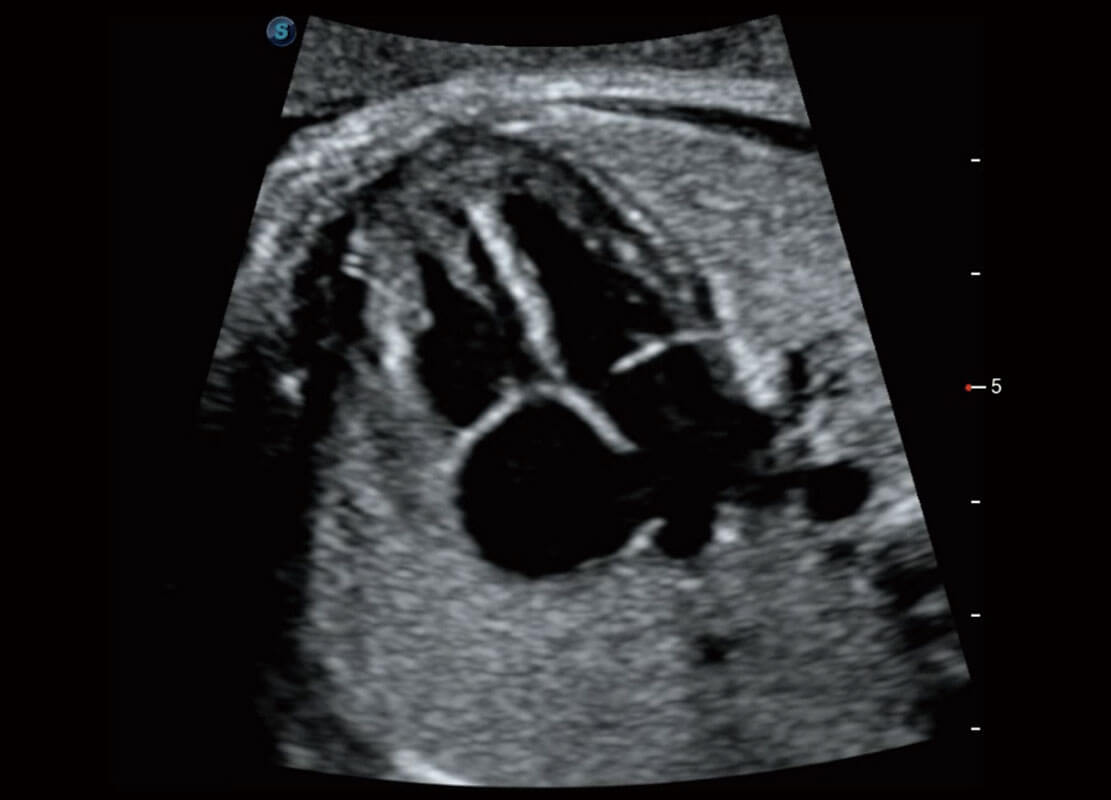

腔内妇科-宫腔分离

腔内妇科-卵巢

腔内三维-宫内节育器

腔内三维-光影成像